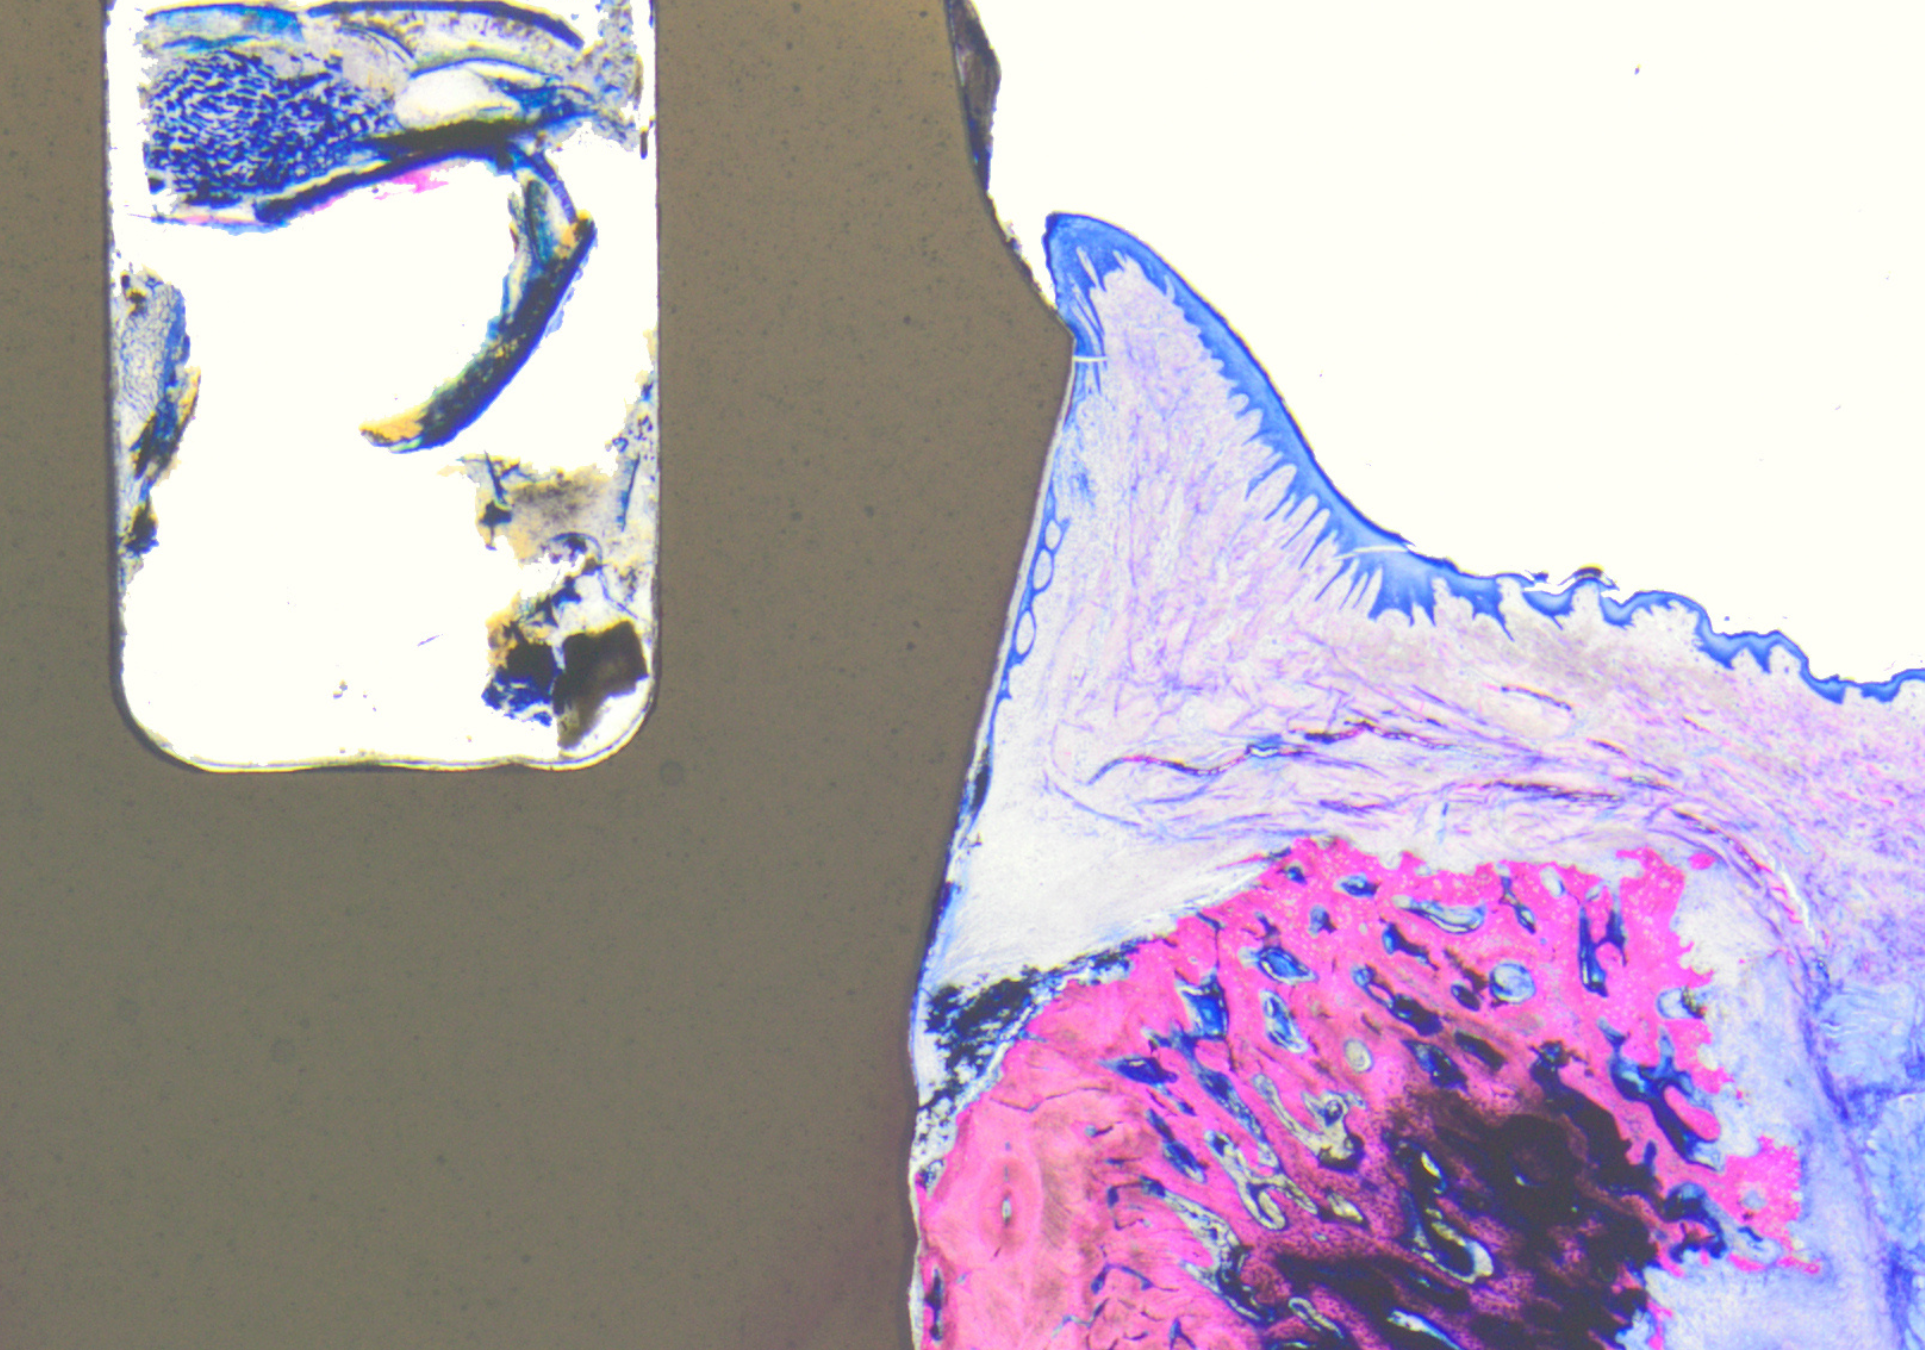

Histology by Dr Peter Schüpbach of a Patent Implant (left) after four weeks of healing: no plaque migration beyond the soft-tissue level is visible, owing to the strong bond (centre) with the transmucosal Patent surface. (Image: Dr Peter Schüpbach)

The world’s first demonstrated bond between peri-implant soft tissue and a transmucosal synthetic surface has been achieved with the Patent Dental Implant System.

Histological investigations by a Swiss research group have shown that epithelial cells begin to attach to the transmucosal Patent surface already in the early stages of healing, creating a strong soft-tissue bond. This process is attributed to the surface’s mucophilic and cell-occlusive properties. The findings were presented in May during a scientific session at EuroPerio11 in Vienna in Austria but have not yet been published.

Unique to Patent Implants, this novel cell bond acts as a dynamic defence barrier, protecting peri-implant tissue against bacterial invasion, inflammation and disease progression.